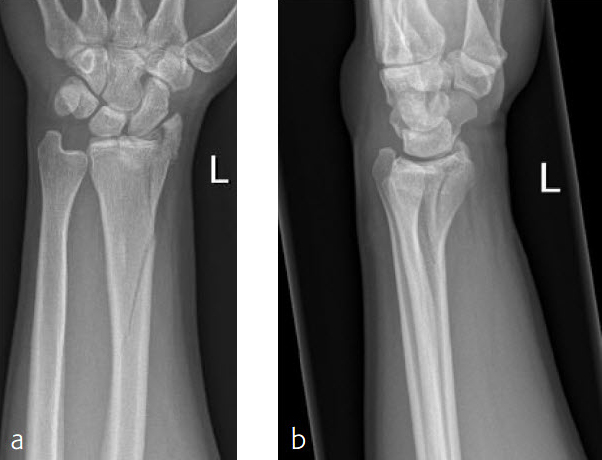

Fig 1a-b Preoperative x-rays.

Fig 1ab Preoperative x-rays.